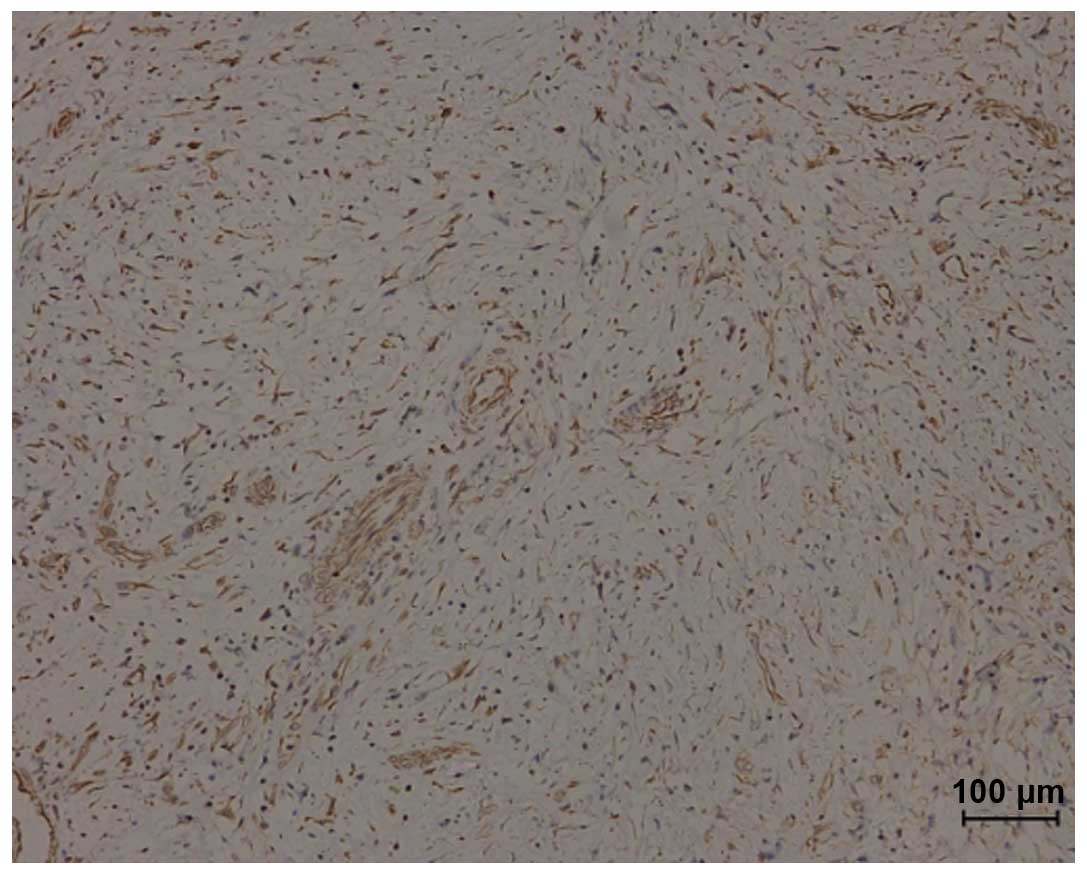

Immunohistochemistry revealed that the SCC component was strongly positive for cytokeratin (CK) and the spindle cell component was strongly positive for vimentin (VM; Fig. 9). Reactivity for epithelial membrane antigen (Fig. 8), Ki-67, smooth muscle actin and actin were detected at various levels. No immune activity was observed for desmin, CD34 or CK7. Additional immunohistochemical data is demonstrated in Table II. Case one (with lymph node metastasis) exhibited well-differentiated SCC on the left side of the neck, however, there was no evidence of metastases in the other two cases.